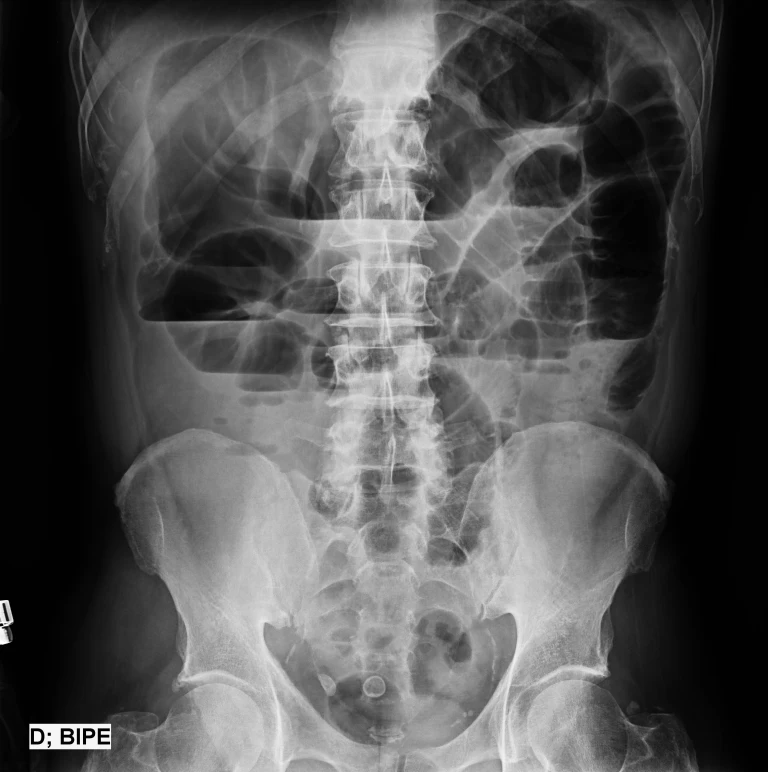

• El estudio radiológico de elección para confirmar el diagnóstico son radiografías simples en decúbito dorsal y de pie, la placa simple en decúbito dorsal muestra asas del intestino delgado dilatadas (más de 3 cm de diámetro), éstas pueden ser múltiples y en diferentes partes del abdomen, o sólo una o dos en un sitio específico.

• La placa simple de abdomen de pie; en el caso de íleo biliar, en el cual el lito que pasó al duodeno a través de una fístula bilioentérica se “atora” en la válvula ileocecal. Cuando la obstrucción se encuentra en el intestino delgado no se observa aire en el colon en ninguna de las placas tomadas.

• Niveles hidroaéreos: Signo de pila de monedas

• Asas dilatadas (asa proximal): Intestino Delgado > 3 cm e Intestino Grueso > 5 cm de diámetro. Asas colapsadas o de calibre normal asa distal.

• Cuando existe necrosis intestinal la radiografía evidencia asa intestinal inmóvil a los cambios de posición y su contenido lleno de gas (negro)

• Son útiles para identificar cuerpo extraño que sean el origen de la obstrucción